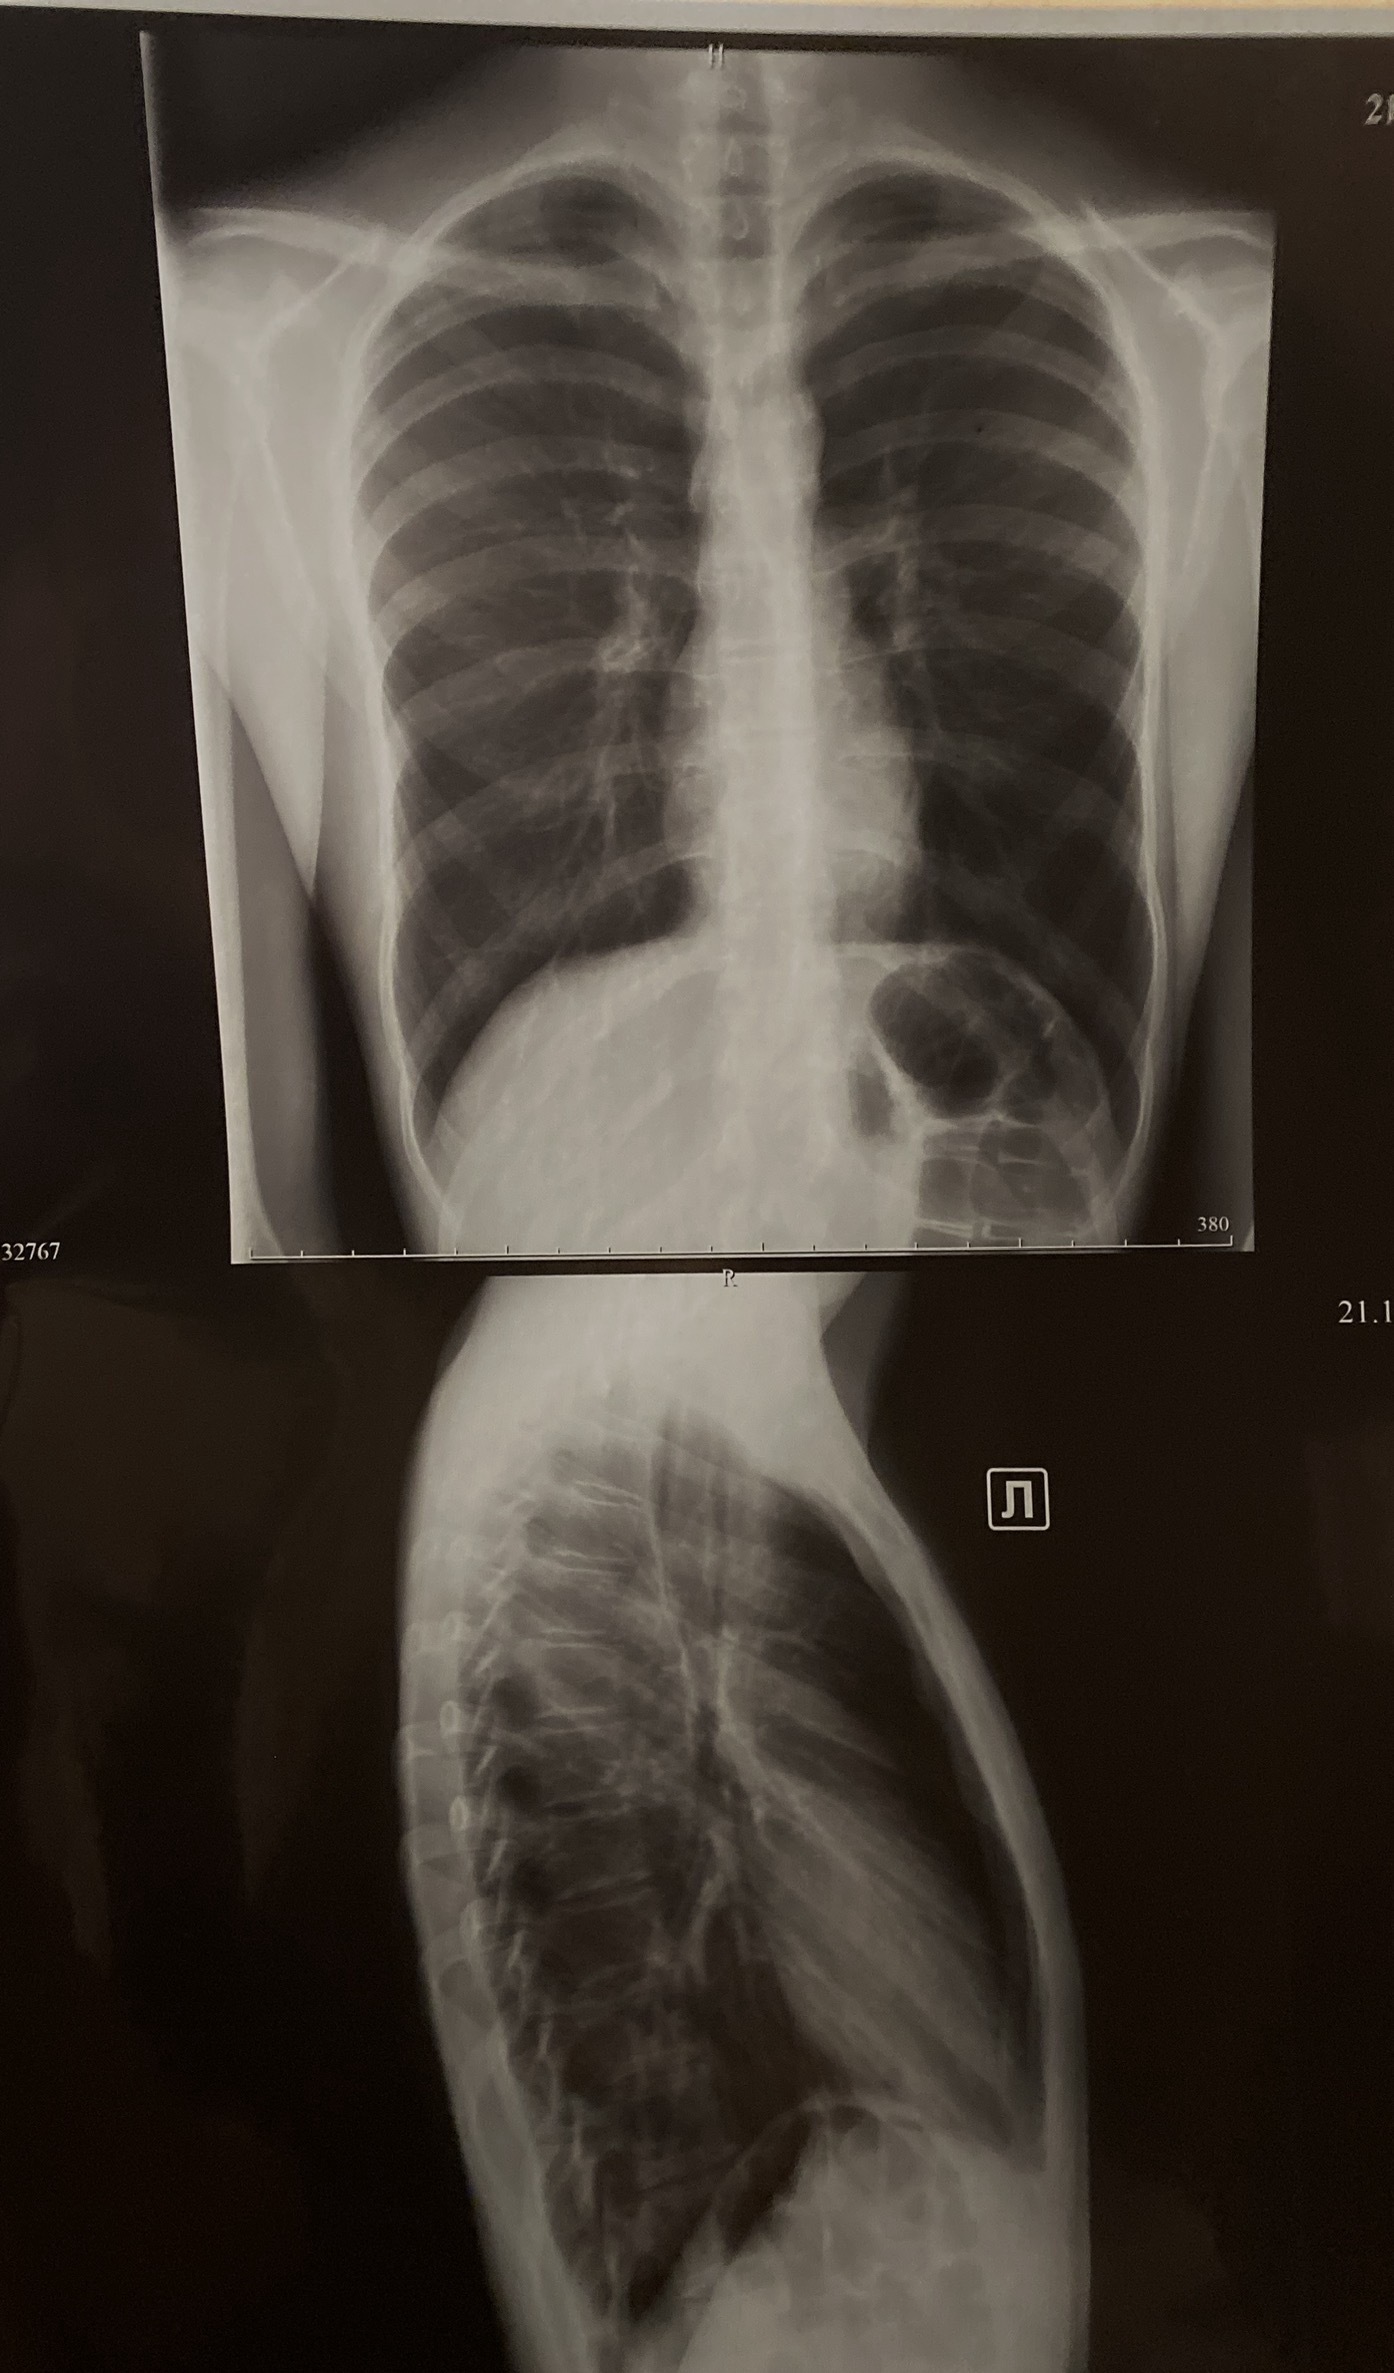

4 user11257984 4 дня назад Лига врачей Так есть ли увеличение ВГЛУ или нет? Терапевт сказал, что на снимке есть увеличенные лимфоузлы в легких, а рентгенолог в заключение написал что вглу нет, кто может подсказать правду [моё] Вопрос Спроси Пикабу Медицина Рентген Лимфоузлы 1 Ещё 0